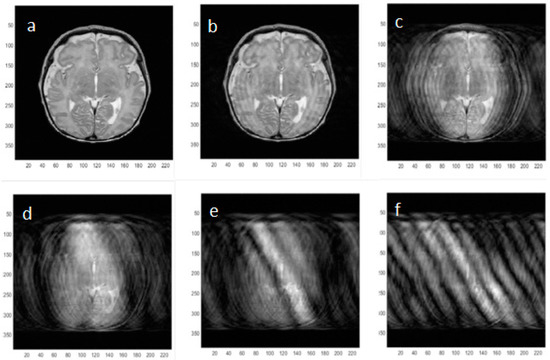

Nodding and side-to-side motions are also important in creating artifacts on neonatal MRI but in this feasibility study we chose to restrict the motion to just one dimension using axial image acquisition only. Different modes of one-dimensional motion are illustrated in Figure 2 [11]. By choosing either sagittal or coronal image planes, head nodding backwards and forwards or side to side could also be corrected using this method.

Figure 2. Different modes of neonatal head motion which could be corrected using one dimensional angular information from the wireless accelerometer. Extension to oblique orientations and to full 3D correction should also be possible but requires further work on the reconstruction algorithm.